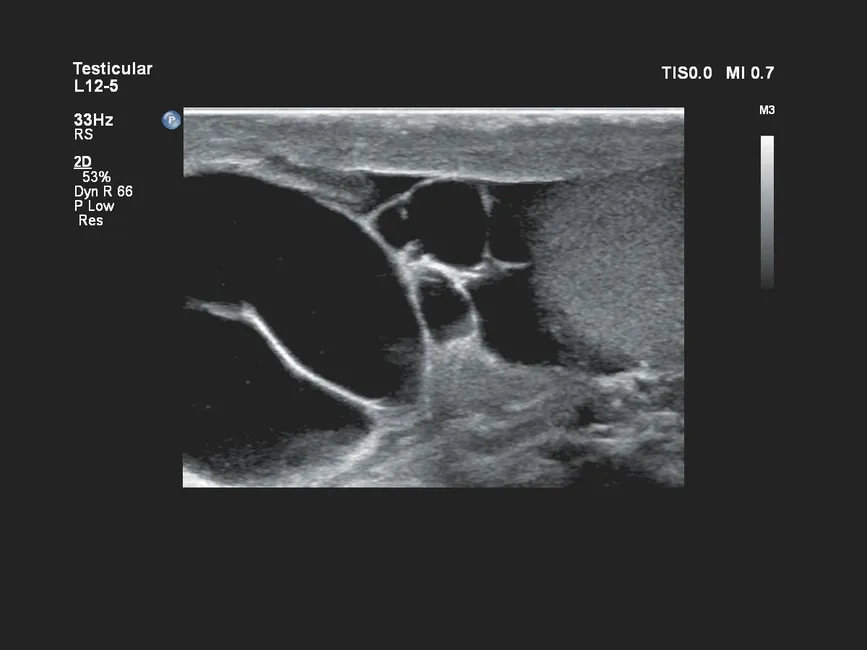

| L12-3 | 3–12 | Broadband линейный датчик | 160 | Сосудистые исследования, исследования мелких органов и поверхностных структур |

- Исследования опорно-двигательного аппарата, мягких тканей и периферических нервов.

- Педиатрические исследования органов брюшной полости, сосудов, мягких тканей.